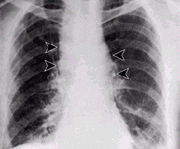

Plicní anthrax

Plicní anthrax se vyznačuje vysokou úmrtností, bez lékařského zákroku končí téměř vždy smrtí. Aby byl lékařský zásah úspěšný, vyžaduje včasnou diagnózu. Příznaky se podobají nejdříve silné chřipce, pak silnému zápalu plic. Léčba probíhá za pomoci silných dávek antibiotik. Letální dávku představuje 10–20 tisíc spor, inkubační doba se pohybuje mezi jedním a několika dny. V anglicky mluvících zemích se tato nemoc může někdy nazývat Wool-sorters' disease (nemoc třídičů vlny), český ekvivalent je „hadrářská nemoc“.